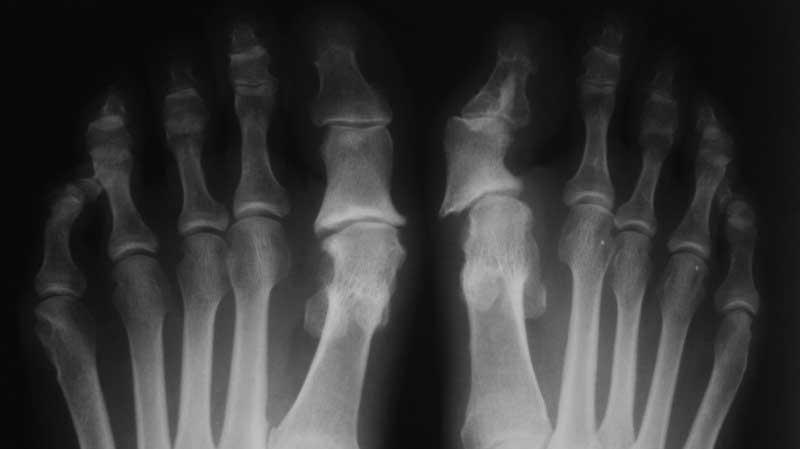

Подвывих пальца кнутри в данном случае вероятнее всего обусловлен наклоном линии опила основания основной фаланги. В принципе - классические показания для артродеза. Если думать о сохранении подвижности плюснефалангового сустава, то можно резецировать основание фаланги, изменив угол наклона опила. Заодно уйдет медиальный экзостоз. Сустав зафиксировать в положении легкой гиперкоррекции спицей или повязкой, что больше нравиться. Повязка удобнее, проще подправить положение пальца в процессе наблюдения.

Рисунок1.jpg

52KB (54081 bytes)